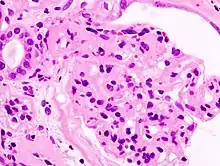

_HE.jpg.webp)

| Microscopic image of diabetic glomerulosclerosis, the main cause of nephrotic syndrome in adults. | |